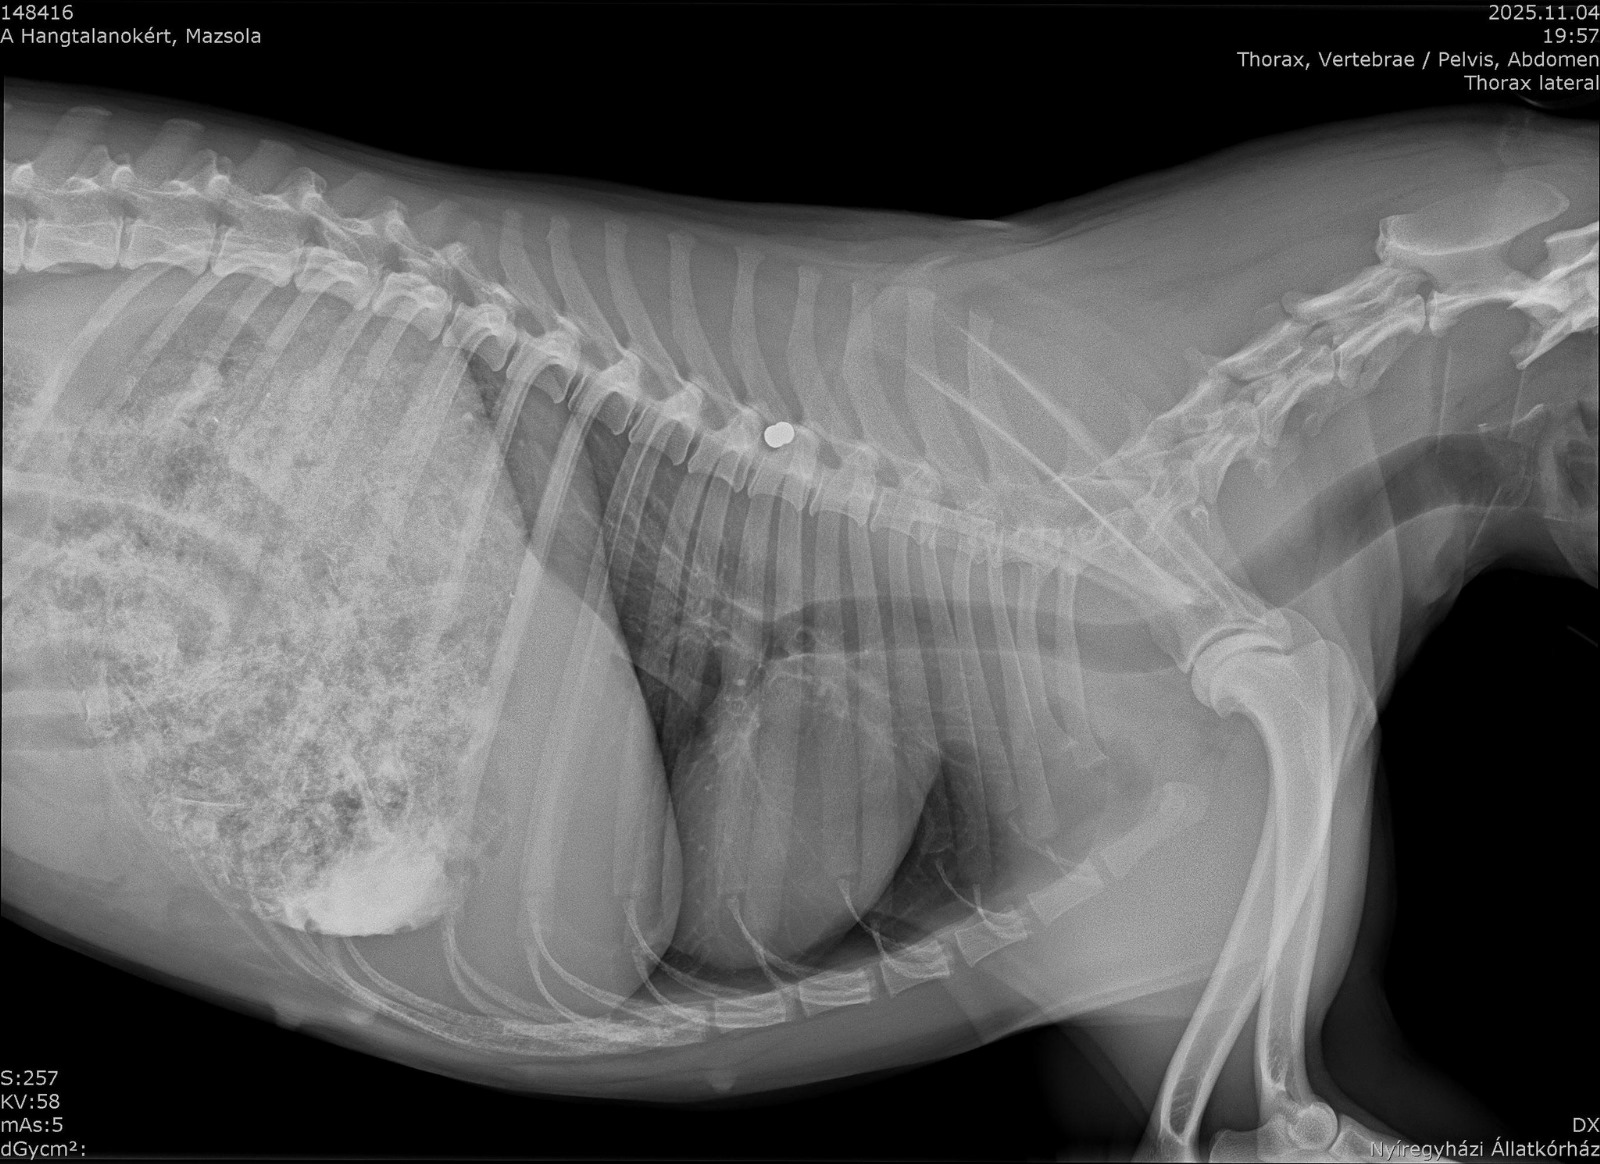

Vorgestern Abend fand ein ungarisches Pärchen eine offensichtlich verletzte Hündin auf der Straße liegend. Sofort war klar, dass sie ihr helfen. Mit dem Verdacht, dass Mazsola (so wurde sie nun getauft) von einem Auto angefahren wurde, ging es in die Tierklinik. Die dortigen Untersuchungen brachten jedoch viel schlimmeres hervor. Auf Mazsola wurde insgesamt 3 mal geschossen! 2 Patronen eines Luftgewehrs steckten in ihrem Körper und die Patrone eines Jagdgewehrs. Ein grausamer Mensch hat die Hündin gezielt verletzt und zum sterben liegen gelassen! Maszolas Zustand war so kritisch, dass sie operiert werden musste. Die dritte Kugel hat ihre Harnröhre, Blase und Gebärmutter durchbohrt… Die Gebärmutter wurde entfernt, die Blase und Harnröhre vernäht. Mazsolas Zustand ist äußerst schlecht und zum jetzigen Stand ist unklar, ob die Hündin überleben wird. Wir hoffen sehr, dass Mazsola große Schutzengel hat und ihr Kämpferwille ungebrochen bleibt!